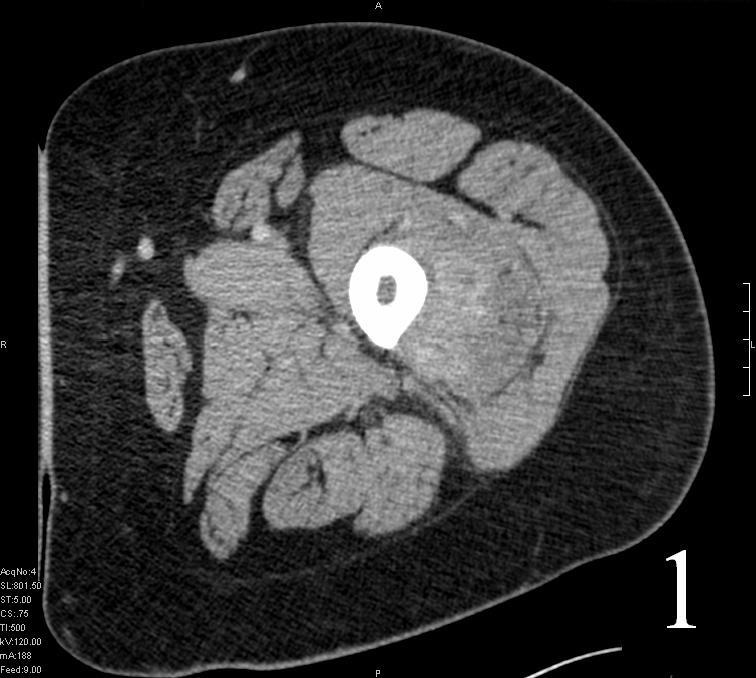

GENERAL INFORMATION Tumoral calcinosis is a very rare entity, characterized by large tumorlike calcium deposits and painless mass, arising near to the articular soft tissue areas. Common areas affected are elbows, hips, knees rarely involve hands and feet. No obvious...